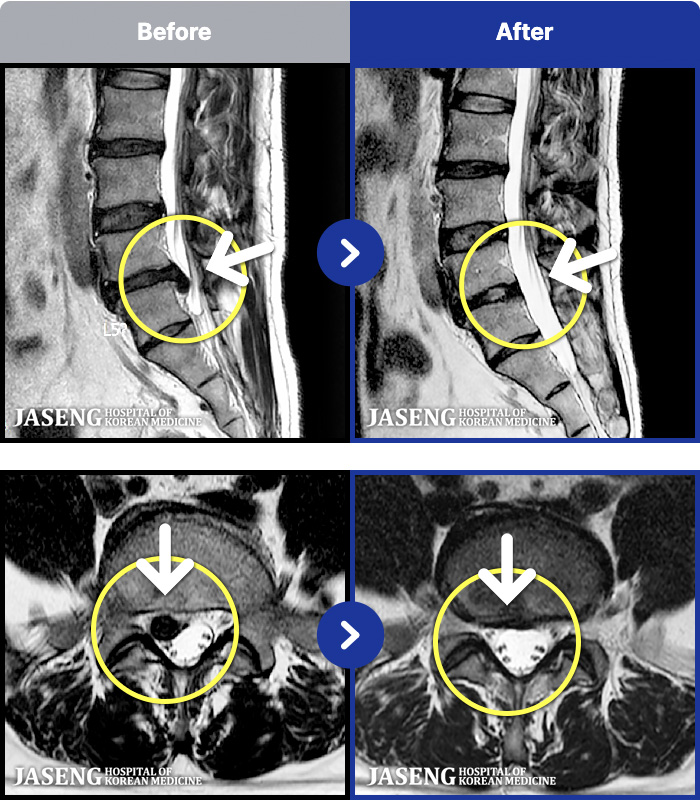

- MRI ġ

MRI ġ

1,301 MRI ũ ʸ Ȯϼ.